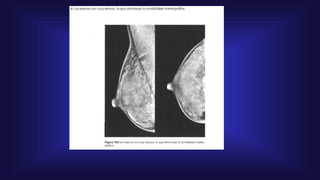

Ecografía mamaría

• La principal ventaja de la

ecografía es su inocuidad

sobre el paciente y su bajo

costo.

• Elimina la sospecha de una

imagen mamográfica poco

clara.

• Diferencia quistes simples y

complejos, fibroadenomas y

carcinomas